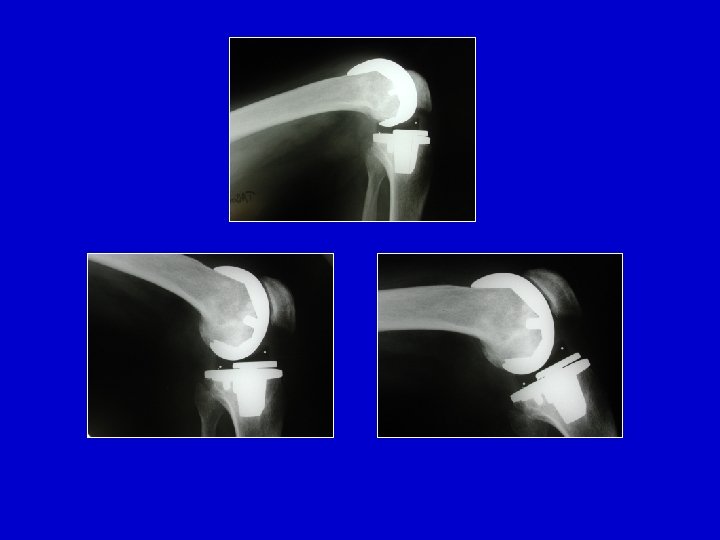

Nei soggetti con più di 65 anni : Protesi unicompartimentale o totale

Necrosi del condilo femorale

Necrosi del condilo femorale Trapianto + Protesi